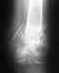

Просто у меня тоже открытый перелом нижней трети левой голени. Сейчас прошло 2 месяца после операции (остеосинтез б/берцовой кости штифтом). По снимкам мой врач говорит, что вокруг перелома образовывается костная мозоль, но хорошо еще видна трещина. И категорически советует вообще не давать нагрузку на ногу еще в течении месяца... А может все-таки можно ногу нагружать?